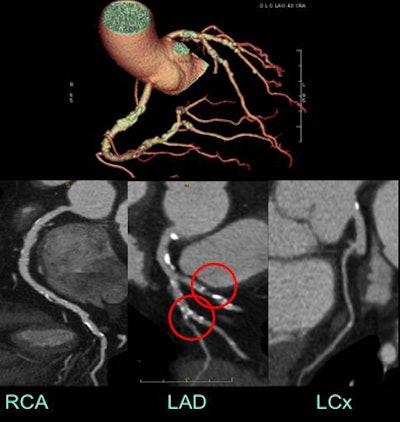

| High coronary calcium scores did not impede most diagnoses. Above, all 17 coronary artery segments were assessable at CTA in a 63-year-old man referred with abnormal myocardial perfusion, chest pain, and a calcium score of 3,215. Images were acquired at 650 mA, 120 kV, 50 msec padding, and an effective dose of 2.53 mSv. Conversely, three segments in the case below were not assessable in a 57-year-old man with a calcium score of 2,318 presenting with shortness of breath and chest pain. CTA was acquired at 750 mA, 120 kV, 75 msec padding, and an effective dose of 5.34 mSv. |

![]() |